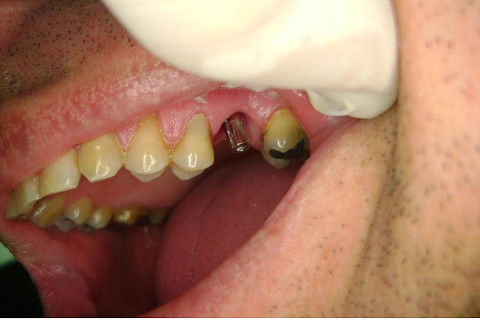

Instalação de um implante em região do 26. Utilizamos um implante cone morse Alvim Neodent 4.3 X 11,5. Foi uma cirurgia muito rápída e minimamente traumática, sem retalho e sutura.

Fotos do caso